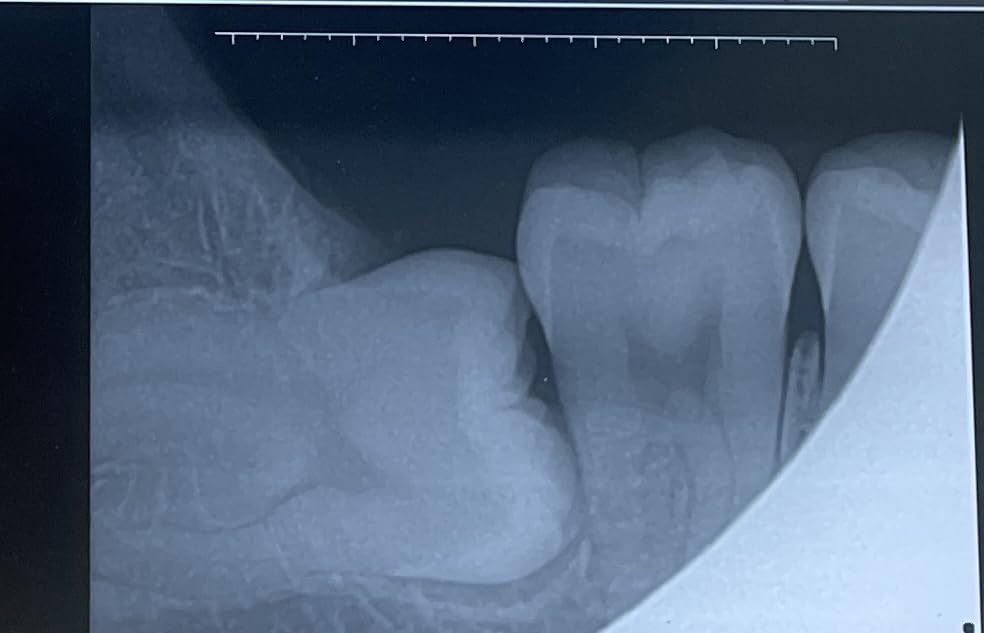

This sensor impressed me with its incredibly fast 3-second image acquisition time. In a busy small practice, every second counts, and being able to capture and display images almost instantly significantly improved my workflow efficiency. The USB 2.0 connection delivered sharp, clear images that made diagnosis straightforward. I tested this sensor with various dental imaging software and found it universally compatible.

The one-hand positioning system is brilliantly designed for stability. During my testing, I appreciated how easily I could position the sensor while maintaining patient comfort. The 16-bit dynamic range produced images with excellent contrast and detail, revealing even subtle pathology. The IP67 waterproof rating gives peace of mind during cleaning and sterilization procedures.

Technical specifications include a dynamic range of 16 bits, which is exceptional for diagnostic imaging. The USB 2.0 interface ensures reliable data transfer to your computer system. The sensor dimensions are compact at 8.3 x 5.9 x 2.6 inches, and at just 12.8 ounces, it’s comfortable for patients to hold in place. The one-click installation software makes setup straightforward even for non-technical staff.

This premium portable unit delivers exceptional image quality thanks to its super high frequency technology operating above 400kHz. During my testing, the difference in image clarity was noticeable compared to standard frequency units. The single-ended solid insulation technology contributes to sharper, more detailed X-rays that make diagnosis more confident. I was particularly impressed by the versatility – this unit works with film, fluorescent plates, and flat panel detectors.

The battery life is outstanding, delivering over 300 exposures per full charge. In a small practice setting, this means you can easily handle a full day’s patient load without worrying about recharging. The technical specs are professional-grade: 60KV tube voltage, 2mA tube current, and exposure times adjustable from 0.01 to 2 seconds. Radiation leakage is minimized below 0.25mGy/h at 1 meter.

What sets this unit apart is the sensor resolution of 12-14lp/mm, which is excellent for diagnostic detail. The USB 2.0 sensor connection ensures fast image transfer to your computer system. The IP67 waterproof rating on the sensor means it can withstand rigorous cleaning protocols. This unit is currently ranked #1 in Dental X-Ray Film Processors, reflecting its popularity among dental professionals.

This complete package pairs the premium XR-A portable unit with a larger digital sensor, making it an ideal all-in-one solution for small practices. The big sensor offers a 2.5x3cm imaging area, which is significantly larger than standard sensors. During my testing, this larger area meant fewer retakes and better coverage for adult patients. The 5mm sensor thickness is slim enough for patient comfort while maintaining durability.

The technical specifications match the premium XR-A unit: super high frequency technology above 400kHz, 60KV tube voltage, and 2mA tube current. What makes this package special is the inclusion of both sensor size options – you get the standard 2.1×2.1cm sensor for pediatric patients and the larger 2.5x3cm sensor for adults. This versatility is invaluable for small practices serving diverse patient populations.

The sensor connects via USB 2.0 for fast image transfer, and the IP67 waterproof rating ensures it can withstand rigorous cleaning. The 3-meter cable is extendable if needed, providing flexibility in operatory setup. Sensor resolution of 12-14lp/mm delivers diagnostic-quality images that reveal even subtle pathology. Like other units in this series, you get over 300 exposures per full charge.